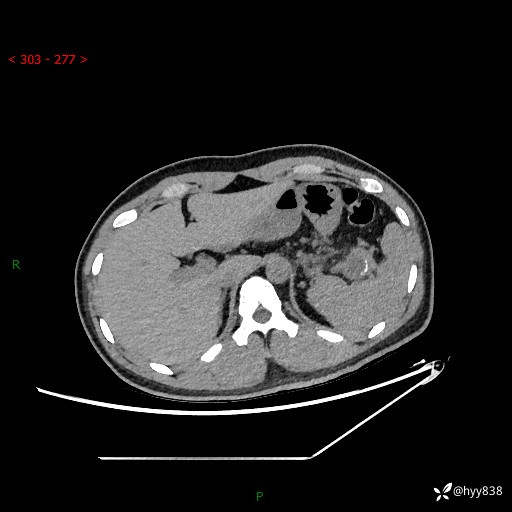

【患者信息】:31岁/男

【主诉】:间断性左下腹疼痛10天

【现病史及既往史】: 患者10余天前无明显诱因出现左下腹部疼痛,呈间断性,无恶心,呕吐,无黄疸,腹泻症状,于当地医院就诊,行腹部C提示:胰腺尾部占位。2型糖尿病。现患者为求手术治疗,门诊以“胰腺肿物”收入院。 患者起病来,一般情况可,大小便正常,体重体力未见明显减轻。

【检查】:胰腺CT平扫+增强